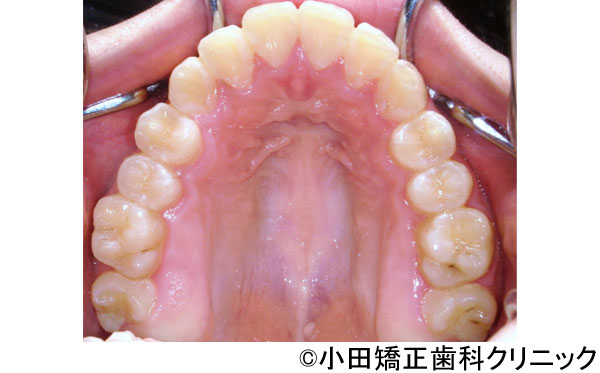

- 治療前

- 治療後

- 呼吸から治して厳しいでこぼこ状態ではあるが、歯を抜くことなくしかも突出のない知的な口元に改善する治療

- 患者様

- 9歳

- 費用

- 1,000,000円(税込)(永久歯治療を含む)

- 期間

- 早期治療2年+永久歯治療1年

治療結果

-

美しい口元、顔立ち、健康的な呼吸をもたらし、鼻呼吸を導く徹底した従来より効果の大きい広げる装置により、厳しいでこぼこ状態を歯を抜くことなく、しかも突出の全くないきれいな口元に改善しました。